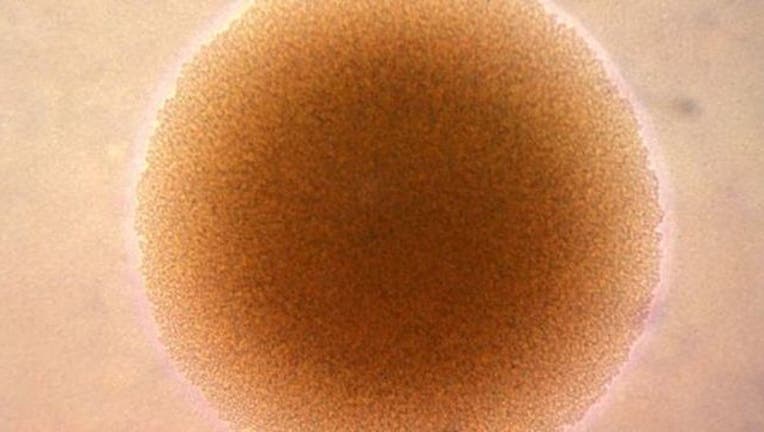

Photomicrograph of Neisseria gonorrhoeae bacteria (CDC/Dr. Stephen J. Kraus)